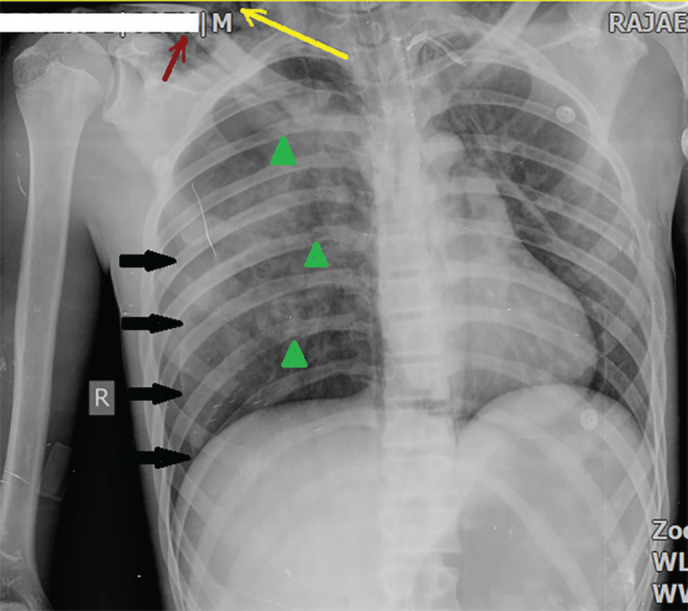

Bronchial rupture following major blunt chest trauma should be suspected in any case of massive and persistent air leak through the intercostal drain tube. Chest radiographs and chest computed tomography scans (CT scans) are highly suggestive of this extremely rare tracheobronchial injury. The present study reported a patient who was a 15-year-old boy. He was a case of a motor-car accident and was brought to the emergency room (ER) of Rajaie Hospital ( Shiraz, Iran) due to dyspnea and chest pain. The physical examination revealed a few crash injuries on his upper extremities, as well as subcutaneous emphysema in his neck. The chest X-ray revealed a right clavicular fracture, multiple rib fractures, a right pneumothorax (but no complete collapse or fallen lung), and also pneumo-mediastinum and subcutaneous emphysema. The chest CT revealed severe pulmonary contusion, severe right-sided pneumothorax, significant pneumo-mediastinum, subcutaneous emphysema, multiple right-side rib fractures, and mild displacement of the right main bronchus. Furthermore, no definitive signs of bronchial rupture were detected. Using a mechanical ventilator, the following parameters were revealed. The maximum pressure (Pmax)=7cm, H2o (was very low), plateau pressure (P. Plateau), and expiratory tidal volume (TV) were not detected due to insufficient amounts. Additionally, increasing TV did not change those values. Bronchial rupture is one of the most important and serious differential diagnoses in forceful chest traumas when the mechanical ventilator reveals low Pmax, very low P.platue, and expiratory TV, with no change in those values with increasing TV.